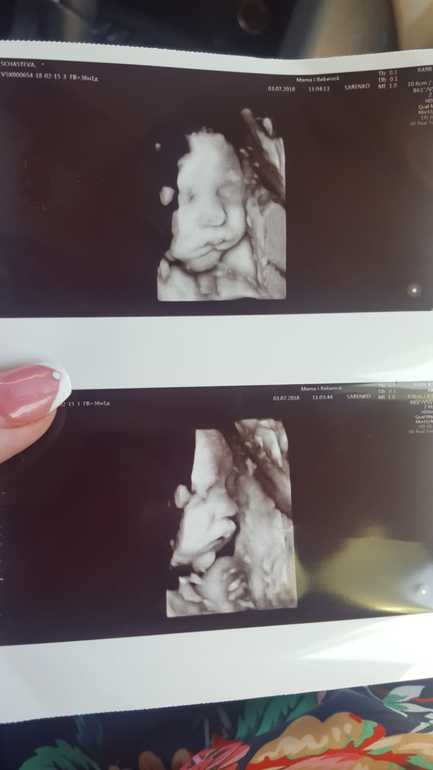

Сходила сегодня на 3д узи) посмотрела на своего карапузика🤗 всё хорошо, соответствуем сроку) весим уже 2907гр.